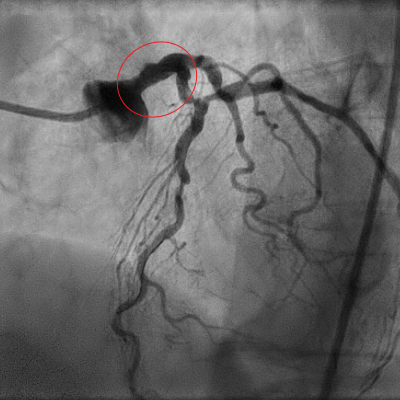

Coronarografia realizată pacientei a evidențiat artera principală a inimii – trunchiul principal coronarian stâng – înfundată în proporție de 99%, ceea ce înseamnă că 2/3 din suprafața cardiacă nu beneficia de o o circulație coronariană adecvată. Acest tip de afectare vasculară cardiacă este principala cauză de moarte subită întrucât nu există nicio șansă de supraviețuire atunci când se înfundă o arteră care presupune un teritoriu implicat foarte mare.

Imaginea 1. Stenoză critică de trunchi coronarian stâng